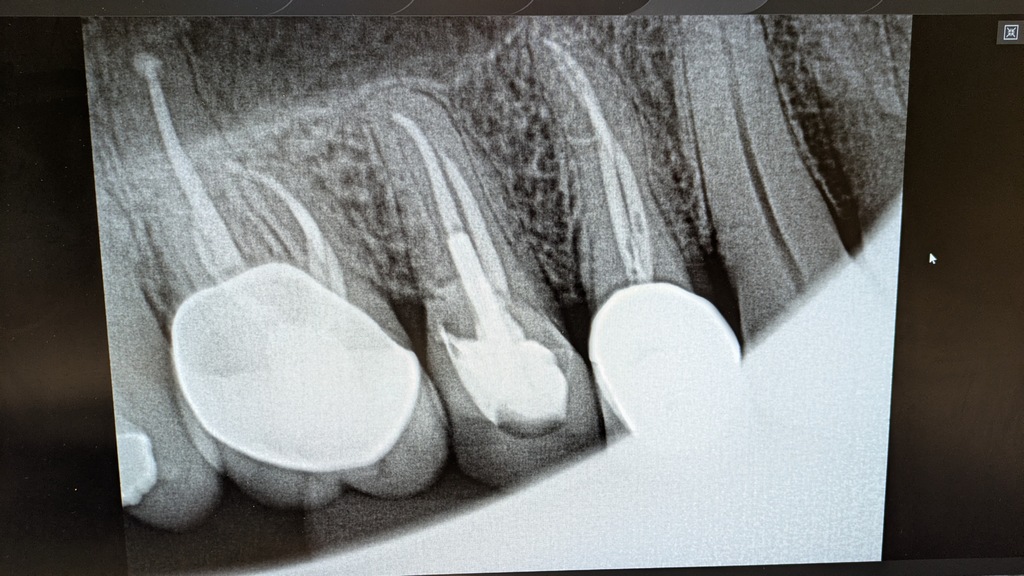

Unfortunately I needed a root canal on #3 in Oct 2024, and on #5 this year (note intricate work on the curved roots), resulting in three dead teeth in a row, but mostly relief from longstanding pains in that area.

0612_RootCanalsOn3-5.jpg (192 Kb) (under photos/25/01_Random/)